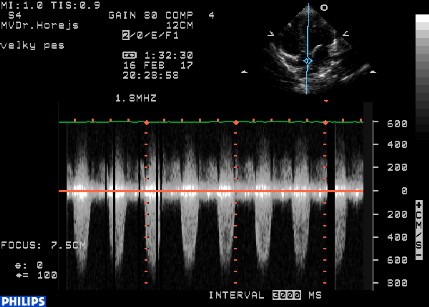

Aortální stenóza